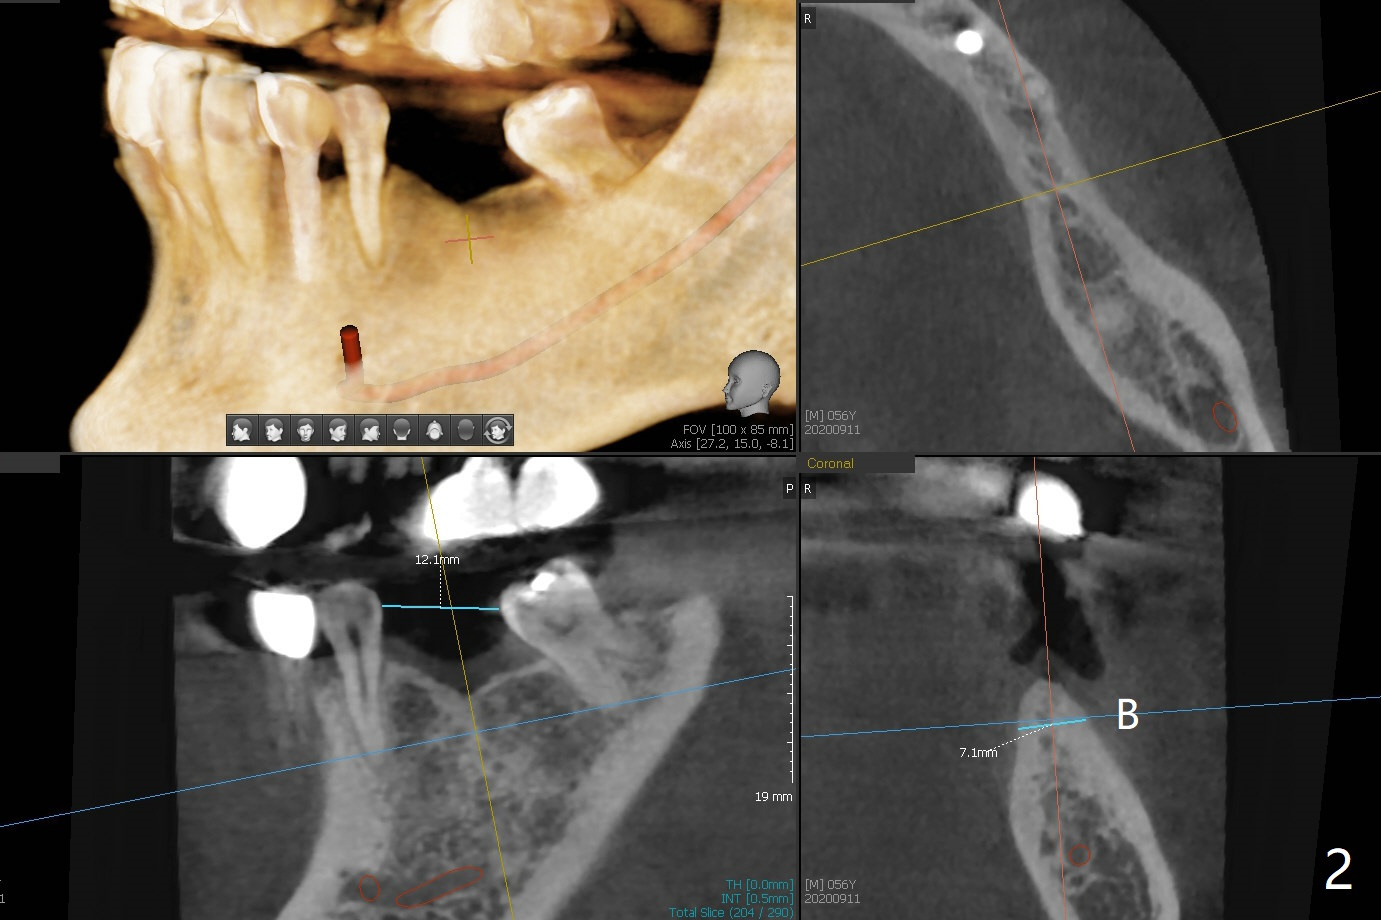

56岁男,高血压,紧张怕痛,要求迅速手术,所以我们初步选择导航。由于他还能在右边咀嚼,先做左侧植牙。左侧好像缺失两个牙齿(图一),不过近远中间隙更象缺失一个牙齿(图二)。牙槽嵴狭窄,骨皮质厚,容易植骨吗?还是容易劈开?牙槽嵴狭窄(图三,四,六)似乎适合种植两个小植体(两个双尖牙)。如果只植入一个,牙槽骨高度差些,植体短(图五),仿佛做牙槽嵴劈开术比较好。